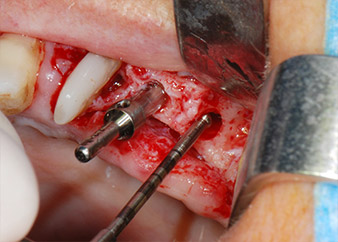

En el siguiente paso, los lechos del implante se prepararon en las posiciones 25 y 26 con instrumentos rotatorios, utilizando un contra-ángulo con un coeficiente de transmisión de 20:1 (WS-75 L, W&H), junto con el nuevo potente motor de implantes Implantmed de W&H (figuras 8 y 19).

A continuación, los implantes (Restore, Keystone Dental, 3,75 mm de diámetro, 8,0 mm de longitud) se colocaron con el motor de implantes (figuras 11 y 12).

Se insertó un implante a baja velocidad

Fig. 11: Se insertó un implante a baja velocidad en la posición 26 y se apretó con un torque limitado a 35 Ncm.